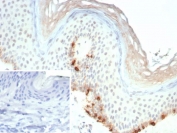

MLANA Antibody human skin IHC staining. Immunohistochemistry analysis of Melan A (MLANA) in FFPE human skin using MLANA Antibody / Melanocyte Lineage Marker Antibody clone rMLANA/9404 demonstrates cytoplasmic HRP-DAB brown staining in melanocytes localized along the basal layer of the epidermis, consistent with melanocyte lineage distribution, while surrounding keratinocytes and dermal cells remain largely negative. The staining pattern highlights discrete melanocyte populations with clear localization and minimal background signal. The inset shows a negative control with PBS in place of the primary antibody, confirming staining specificity. Heat-induced epitope retrieval was performed using pH 9 Tris-EDTA buffer for 20 min prior to staining.